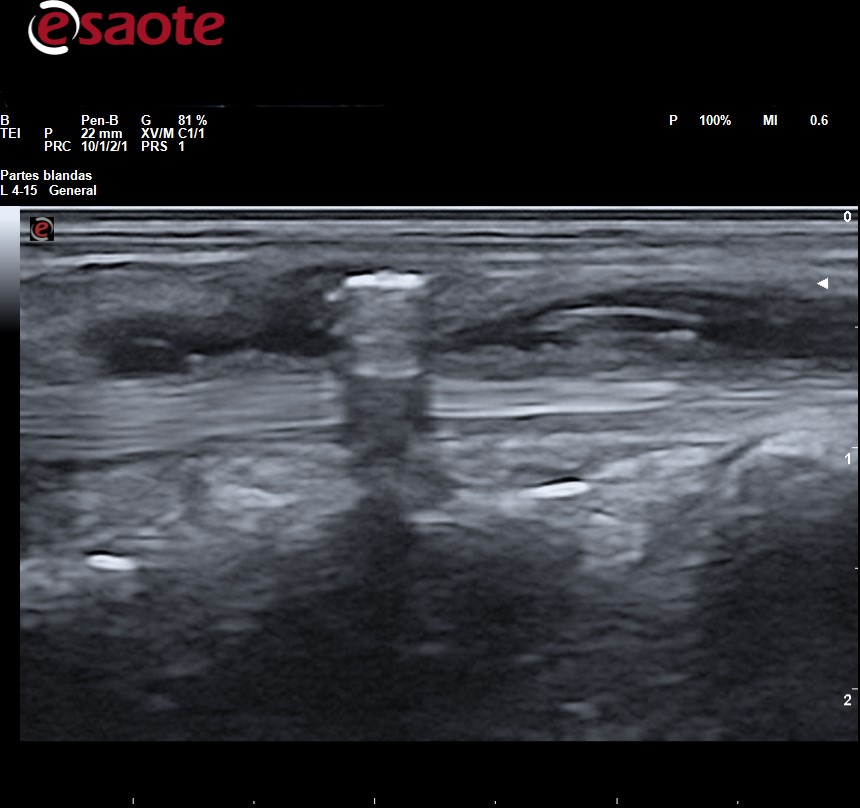

Observamos en el tejido celular subcutáneo imagen lineal hiperecogénica con artefacto de reverberación

La Rx es la primera técnica de diagnóstico para identificar y localizar cuerpos extraños, sin embargo, en ella solo pueden apreciarse la presencia de fragmentos radiopacos (metal, vidrio, piedra y algunos plásticos). Los fragmentos de madera, espinas de plantas y de pescados son indetectables. La Rx da una idea de la ubicación del fragmento y de sus relaciones con huesos y articulaciones adyacentes, pero no puede determinarse la ubicación del fragmento con relación a las estructuras adyacentes: tendones, vasos sanguíneos y nervios que sí podremos determinar con precisión mediante la ecografía lo cual facilita la planificación para su extirpación. Tanto los fragmentos radiopacos como los radiotransparentes se aprecian en ecografía como imagen hiperecogénica con artefacto de sombra acústica posterior o de reverberación según las características del cuerpo extraño rodeada de halo hipo-anecoico si hay granuloma.